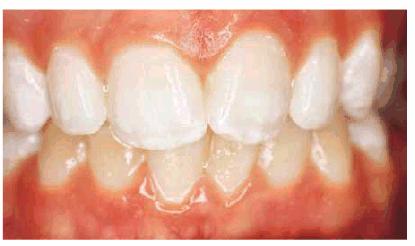

either on an individual tooth or on all teeth (Figures 16-1A, and 16-1B). There are many causes and

Figure 16-1A: An otherwise attractive smile is marred by discolored teeth.

Figure 16-1B: After tooth lightening, the smile is much more pleasing.